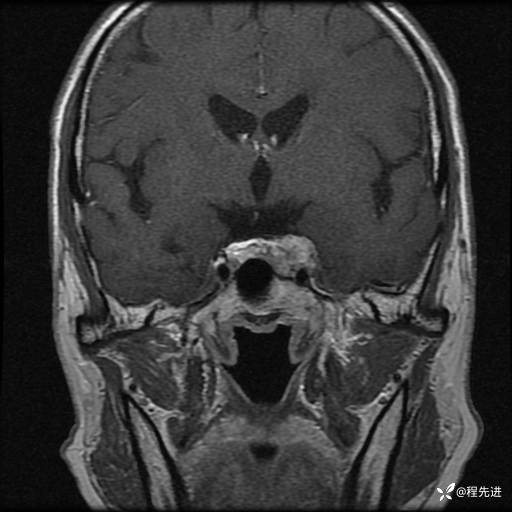

MRI平扫+增强:

T1:

T2:

T1增强: